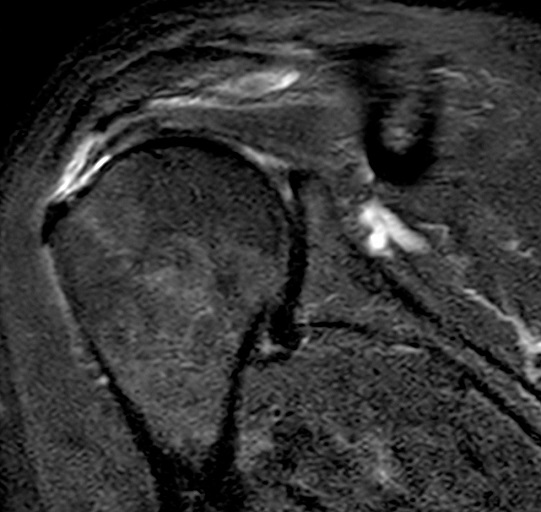

La diagnosi clinica si avvale di decine di test funzionali. La diagnosi clinica non è sufficiente per poter dare indicazioni terapeutiche, poiché non è in grado di stabilire la qualità dei tessuti e la loro riparabilità. A tale scopo il protocollo diagnostico si avvale anche della radiologia convenzionale, dell’ecografia e della RMN (Fig. 2).